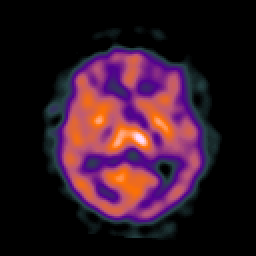

AIDS dementia: overlay -- Slice #9

[Home][Help][Clinical][Tour 1] Slice 9